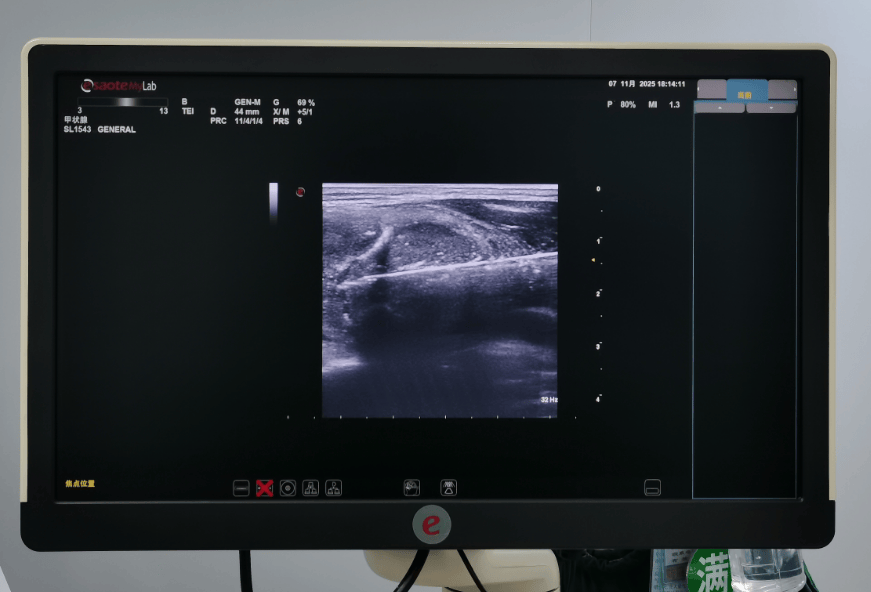

目前常用的是甲状腺微波消融治疗,是微创肿瘤原位治疗技术,是在超高清四维立体定向检查系统监测下,采用微波离子消融针靶向到甲状腺病变组织内(无需开刀),用高频微波粒子将病变的细胞组织破坏灭活,并分解为可被人体代谢分子,短时间内自身吸收、消失,避免了开刀手术的术后等一些列并发症。